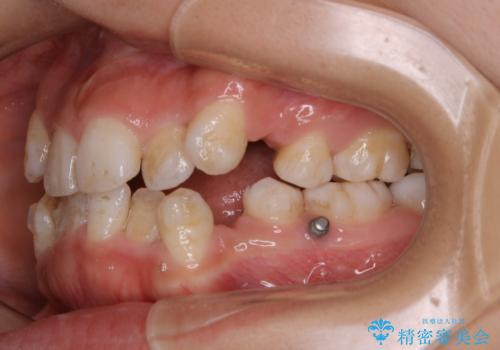

- インビザライン中に、コーヒーによる着色が気になるとのことでした。PMTC60分コースを行いました。

PMTC(保険外治療)は、毎日の歯磨きで落としきれない汚れや、コーヒ、紅茶・タバコのヤニなどの着色も除去します。目には見えない歯と歯の間・歯肉の境目・インビザライン中はアタッチメント周囲などに残っているプラーク(歯垢)もしっかり取り除きます。PMTCでは専門的な機械や材料を使用して、徹底的に汚れを除去するため、虫歯・歯周病・口臭予防などにつながります。